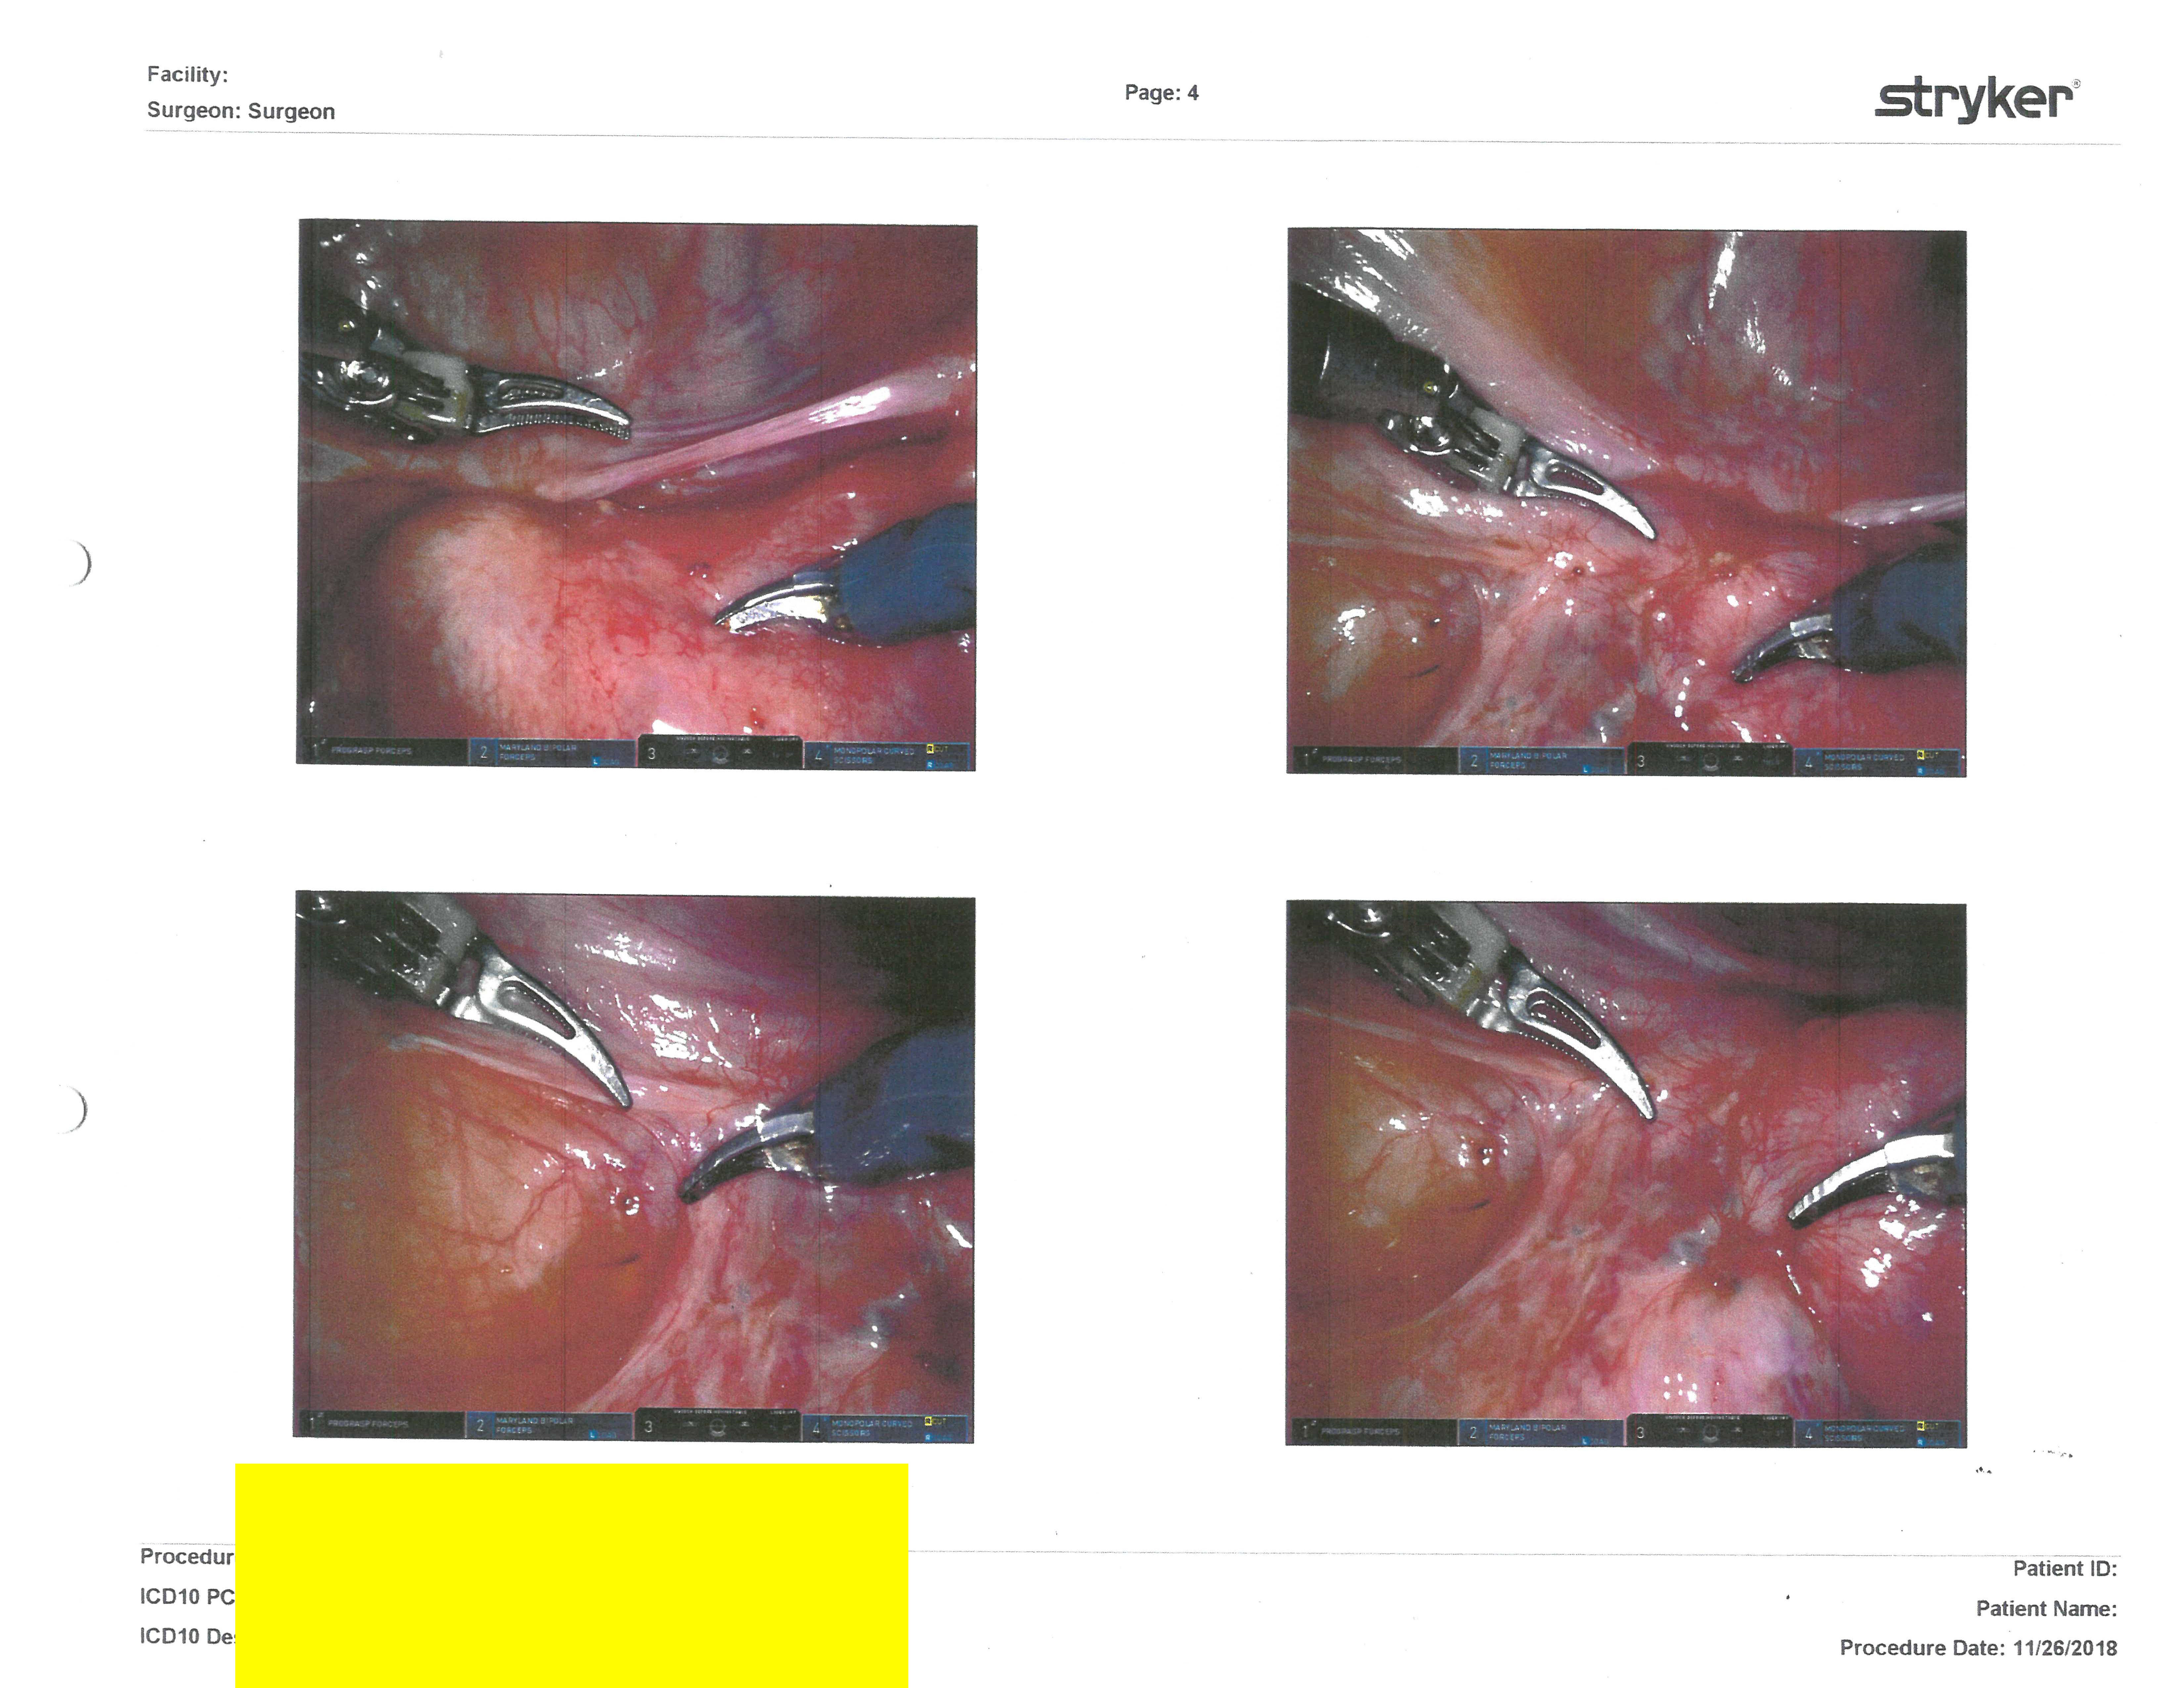

Surgery Photos

But here are the rest of my surgery photos I received at my post-op appointments (click on them to enlarge):